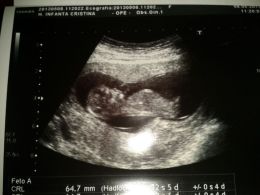

De las cosas más lindas que he experimentado, «la primera ecografía». Yo este momento lo llamo el antes y el después, hasta la semana 11 nadie realmente me había confirmado que un

ser estaba creciendo dentro de mi, lo sabia, pero no existía prueba científica de que esto fuese así, y yo necesito de pruebas, ver para creer, esa soy yo! Así que cuando llego al médico la primera vez, me acuesto en la camilla y empieza a aparecer esa criatura en una pantalla a mi derecha, luego de repente escucho los latidos de su corazón, y ahí es cuando piensas, «mierda, ahí esta, voy a ser mamá». A partir de ahí sólo vi lo maravilloso de ese pedacito de ti que esta formándose dentro y que es capaz de producir tantos sentimientos encontrados, el más fuerte claro esta es el de felicidad.

De las cosas más anheladas, «la segunda ecografía», aquí nos enteramos del sexo y nos enteramos ya con certeza que todo está bien, el bebé se desarrolla con normalidad. con respecto al sexo, yo quería niña y muy al principio ¡me soñé que era una niña! Sólo necesitaba confirmación, y ¡es niña! Todo está bien, esta vez se ha visto mucho mejor todo su cuerpecito, hemos analizado órgano por órgano, sus riñones, su hígado, el corazón, la espina dorsal, el cerebro, las articulaciones, manos, pies, dedos, boca, nariz… En fin es alucinante tanta belleza. ¡Te esperamos con ansia loca Martina!.